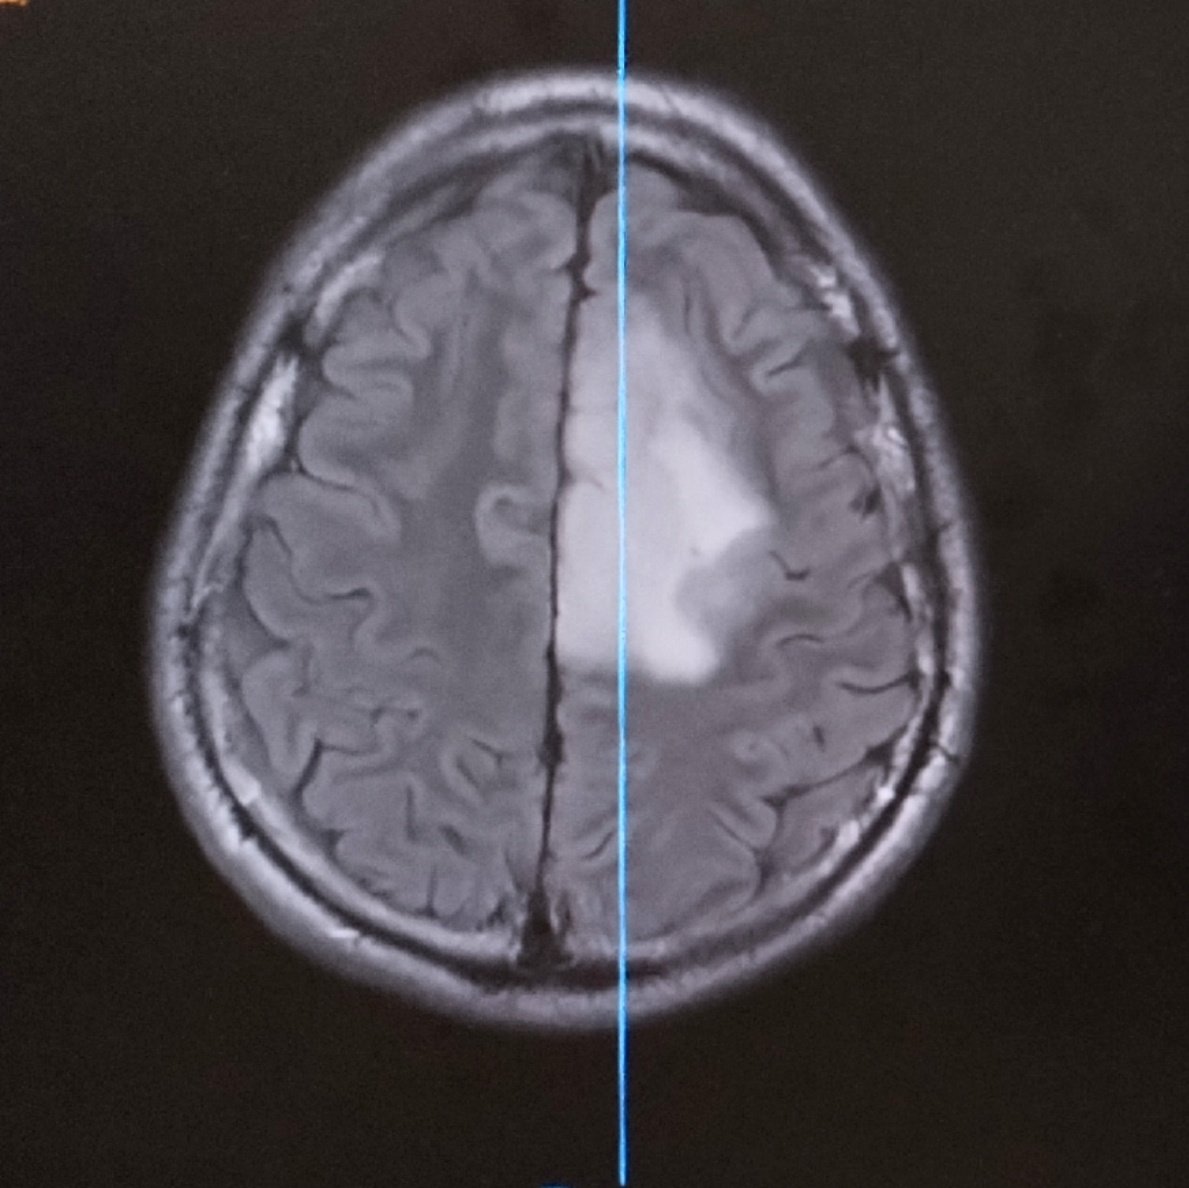

A 25 year old man comes to the emergency room with an acute history of hallucinations, persecutory delusions, aggresive behavior, psychomotor agitation. The mental status examination shows severe cognitive dysfunction. This is the brain image. Thoughts?

Jesus Ramirez-Bermudez tweet media

@JRBneuropsiq Paracentral lobule affection with contralateral lower limb palsy and urinary incontinence perhaps?